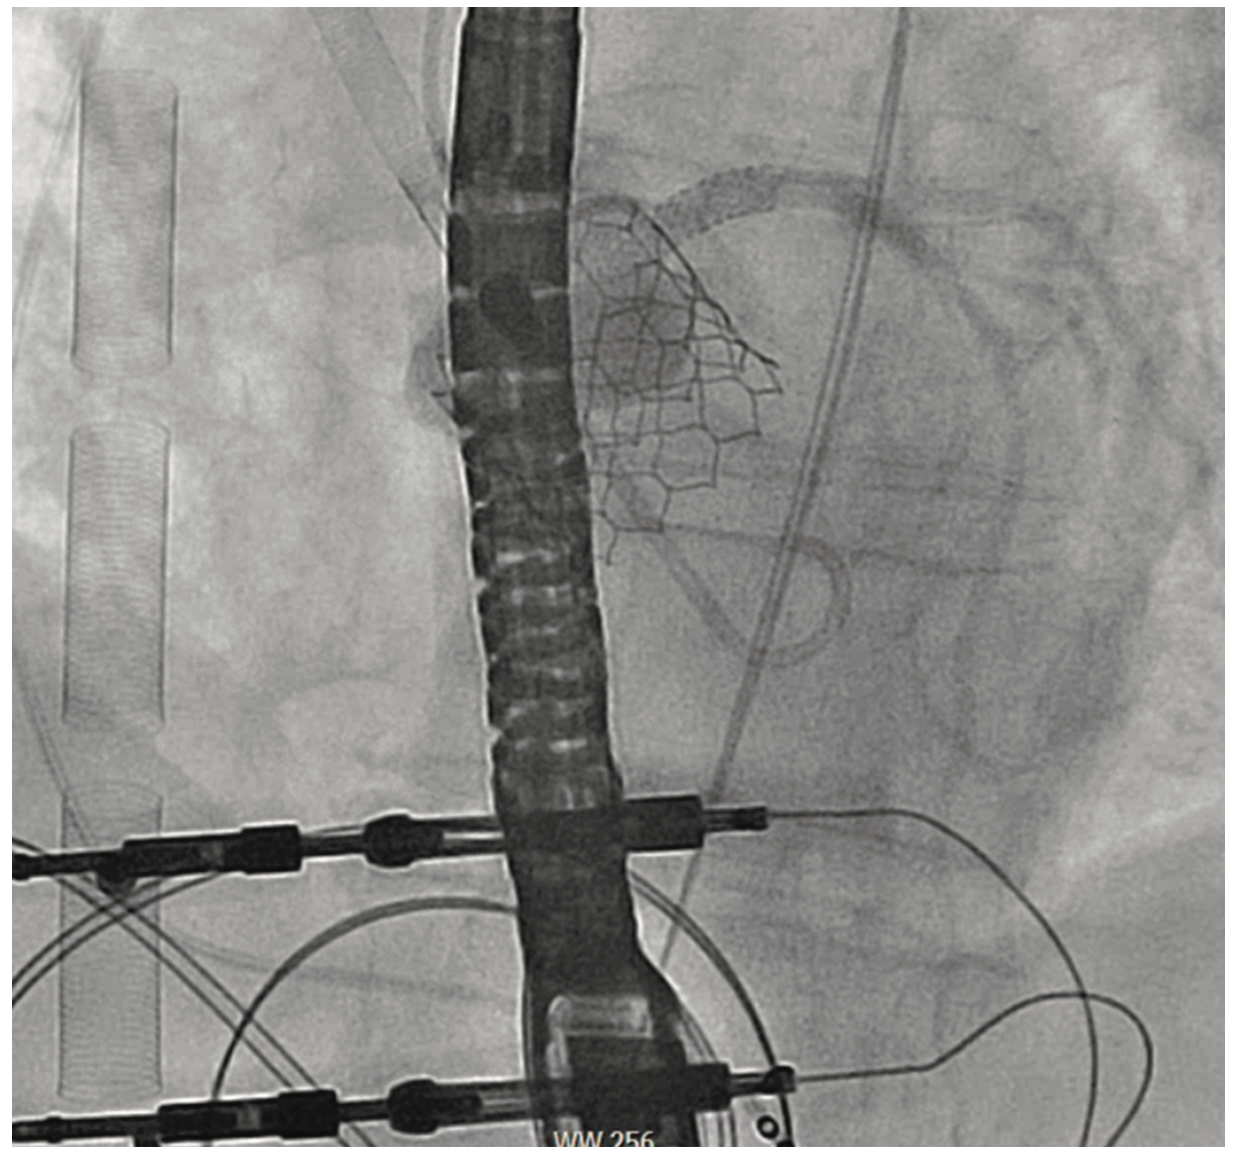

An 81-year-old female with symptomatic severe aortic stenosis, logistic EuroSCORE I (European System for Cardiac Operative Risk Evaluation) of 14.46%, EuroSCORE II of 3.44%, and Society of Thoracic Surgeons (STS) estimated surgical mortality of 3.371%, underwent TAVR. Transthoracic echocardiogram (TTE) showed a heavily calcified aortic valve with a mean gradient of 68 mmHg, aortic valve maximum velocity (Vmax) of 4.2 m/sec, calculated aortic valve area of 0.8 cm2, and normal left ventricular systolic function. Computed tomography angiography (CTA) demonstrated heavily calcified aortic root, leaflets, and annulus. Transfemoral implantation of a 23 mm Sapien 3 (Edwards Lifesciences) valve was performed (Figures 1-2). Using a 20 mm balloon for pre-dilation, the valve was implanted successfully in a 50-50 position (Figure 3). The immediate post-deployment aortogram showed leakage of dye outside the left sinus with no evidence of cardiac tamponade. Despite that fact, the patient developed immediate hemodynamic collapse. QRS widening and ST-elevation were visible on the monitor. Narrowing of the left main coronary artery (LMCA) with reduced TIMI flow (0-1) was evident in angiographic images (Figures 4-5). The patient had a cardiac arrest, cardiopulmonary resuscitation was initiated, and she went into cardiogenic shock. The patient stabilized with the placement of venoarterial extracorporeal membrane oxygenation (VA-ECMO) and the insertion of the Impella device (Abiomed) (Figure 6). An emergent percutaneous intervention was performed within minutes from collapse by the deployment of two drug-eluting stents from the LMCA into the left anterior descending (LAD) coronary artery (Figure 7) using the Culotte technique with final kissing-balloon dilatation. After the restoration of coronary flow, the patient was admitted to the cardiothoracic intensive care unit. She remained stable. The ECMO and Impella implant was removed after 7 days. Postprocedure on day 14, the patient was discharged to a rehabilitation facility. Echocardiography showed a well-functioning valve with acceptable residual gradient and mild to moderate paravalvular leak.